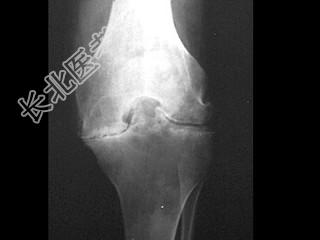

- 单项选择题男,21岁, 慢性膝关节疼痛,活动受限, 皮肤多处青紫,结合图像, 最可能的诊断是 ( )

A、痛风

B、类风湿关节炎

C、退行性骨关节病

D、白血病

E、血友病性关节炎